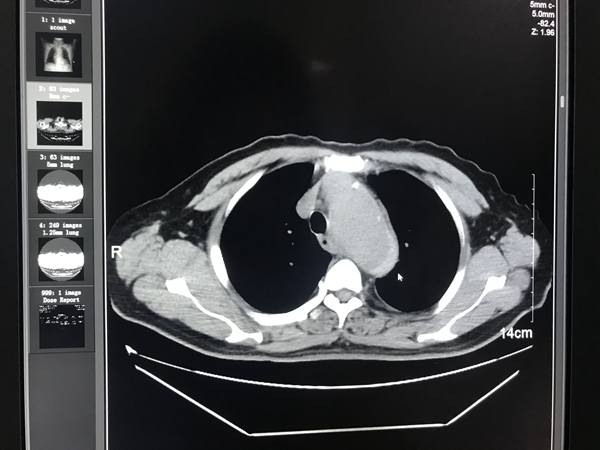

放射科医师范尚文为患者做了CT检查并出具了诊断报告,影像诊断显示:主动脉夹层可能。诊断后,范医师第一时间向科主任江毅军汇报,江主任随即将“危急值”告知施医师,并向医务科报告备案。施医师表示,主动脉是人体动脉的主干道,直接受到心脏泵出的血流冲击,使其内膜承受巨大的血流压力,一旦动脉内膜出现破损,这可是危及生命的“定时炸弹”。

▼史先生的胸部CT